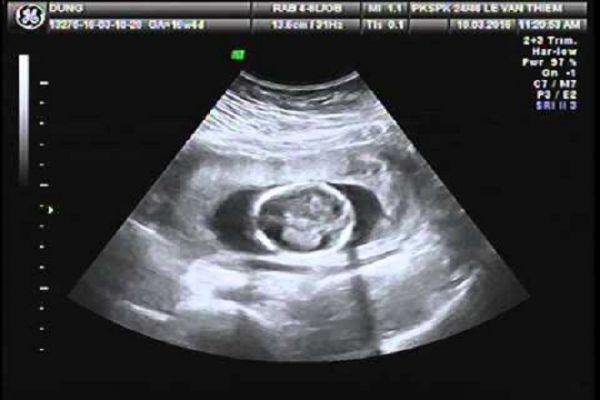

Siêu âm thai nhi là một kỹ thuật hình ảnh có sử dụng sóng âm thanh tần số cao để tạo ra hình ảnh của một em bé trong tử cung. Hình ảnh siêu âm thai nhi có thể giúp nhà cung cấp dịch vụ chăm sóc sức khỏe đánh giá sự tăng trưởng và phát triển của em bé và xác định mang thai đang tiến triển. Siêu âm thai nhi cũng có thể cung cấp cho cơ hội để nghiên cứu hồ sơ của bé và xem nhịp tim của bé trước khi sinh. Trong một số trường hợp, siêu âm thai nhi được sử dụng để đánh giá các vấn đề có thể xác định chẩn đoán.

Siêu âm thai nhi thường được thực hiện trong tam cá nguyệt đầu tiên để xác nhận và ghi ngày tháng mang thai và ba tháng thứ hai - từ 18 đến 20 tuần khi các chi tiết giải phẫu có thể nhìn thấy. Nếu sức khỏe của bé cần được theo dõi chặt chẽ hơn, siêu âm có thể được lặp đi lặp lại trong suốt thai kỳ.

Nhà cung cấp dịch vụ y tế hoặc kỹ thuật viên chăm sóc sẽ di chuyển đầu dò qua lại trên bụng. Các sóng âm phản xạ xương và các mô khác sẽ được chuyển đổi thành hình ảnh đen và trắng hoặc màu xám trên màn hình. Nhà cung cấp dịch vụ sức khỏe hoặc chăm sóc kỹ thuật viên sẽ đo bụng của bé, đầu, xương đùi và các cấu trúc khác. Có thể in hoặc lưu trữ hình ảnh nào đó, tài liệu cấu trúc quan trọng. Có thể sẽ được cung cấp các bản sao của một số hình ảnh.

Tùy thuộc vào vị trí và giai đoạn phát triển của bé, có thể có thể tạo ra một khuôn mặt, bàn tay và các ngón tay, hoặc cánh tay và chân. Đừng lo lắng nếu không thể "nhìn thấy" em bé. Hình ảnh siêu âm khó khăn cho một người quan sát không được đào tạo để giải mã. Yêu cầu nhà cung cấp dịch vụ chăm sóc sức khỏe hoặc kỹ thuật viên để giải thích những gì trên màn hình.